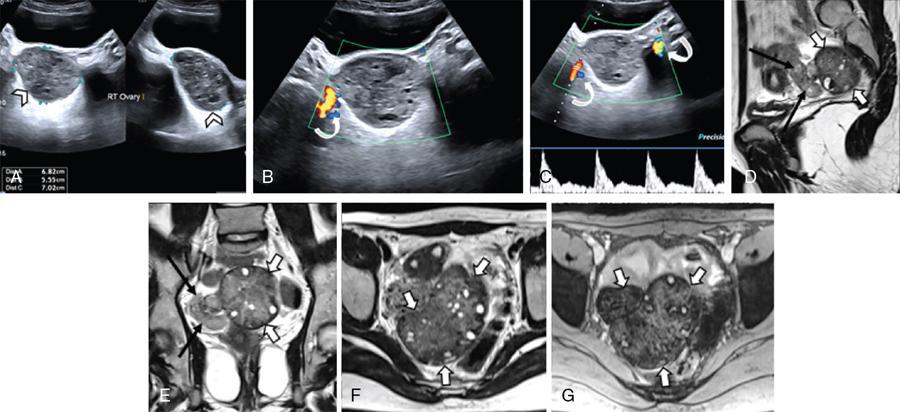

Fig. 11.16.1.5 Ovarian hyperstimulation syndrome with right adnexal torsion: A 30-year primigravida with in vitro conception presented at 8 weeks’ gestational age with severe right lower abdominal pain and vomiting. (A, B and D) T2WI displays grossly enlarged right ovary (arrowheads) with multiple cysts. The ovarian stroma is hypointense on (A, B and D) T2WI and (E) GRE due to haemorrhage (asterisk). (C and F) Presence of a twisted pedicle is noted (short thick arrows). (D) A dilated jejunal loop is seen adherent to the right ovary (curved arrow). (B and F) The left ovary is also enlarged, though to a lesser extent, with multiple cysts (long thin white arrows). Emergency laparotomy with right salpingo-oophorectomy with adhesive band release for torsion of gangrenous right ovary, and small intestinal obstruction was done.

Fig. 11.16.1.6 Corpus luteal cyst with torsion: (A) Grey-scale USG with (B) Doppler in a 26-year primigravida (conceived following treatment for infertility), complaining of sudden severe right-sided pelvic pain at 8 weeks’ gestational age shows an enlarged right ovary with two cysts (arrowheads). No intraovarian flow is seen. However, arterial flow is present in the pedicle (curved arrow). (D–F) T2WI show the enlarged right ovary with two cysts (short thick arrows), one of which has hypointense walls due to haemorrhage, as confirmed on (C) GRE (thin black arrow). (G) Coronal T2WI depicts the thickened and twisted vascular pedicle with the ‘whirlpool’ appearance (thin white arrows). (H and I) Following laparoscopic detorsion with fluid aspiration from the larger cyst, a repeat USG scan with Doppler 2 weeks later shows reduction in the size of the ovary with a collapsed cyst with heterogeneous echoes (asterisk) and (J) revived normal intraovarian vascularity. The patient subsequently had a normal delivery.